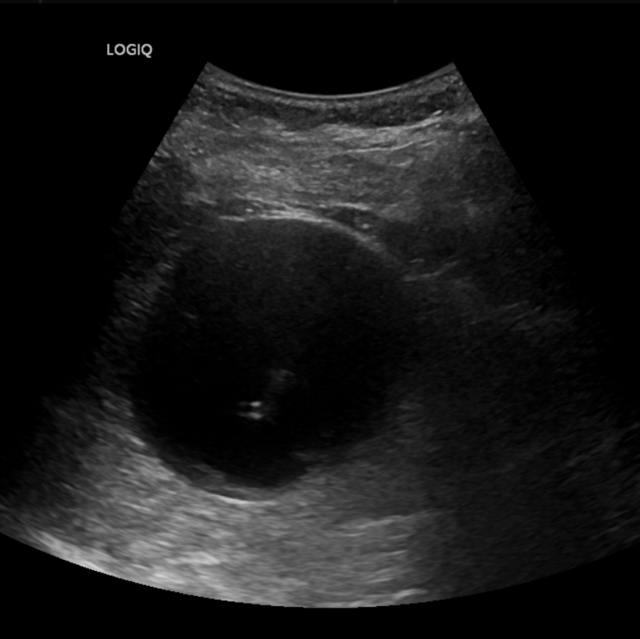

▲患者超声影像

超声介入张轶亮主治医师了解老赵的病情后立刻为其超声检查,发现右肾囊肿确实很大,已经压迫了周围肾组织。